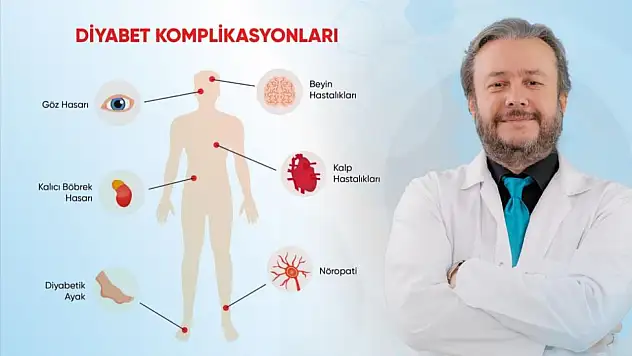

Kontrol altına alınmayan diyabete dikkat!

Diyabet hastalarına uzmanından sıcaklık uyarısı